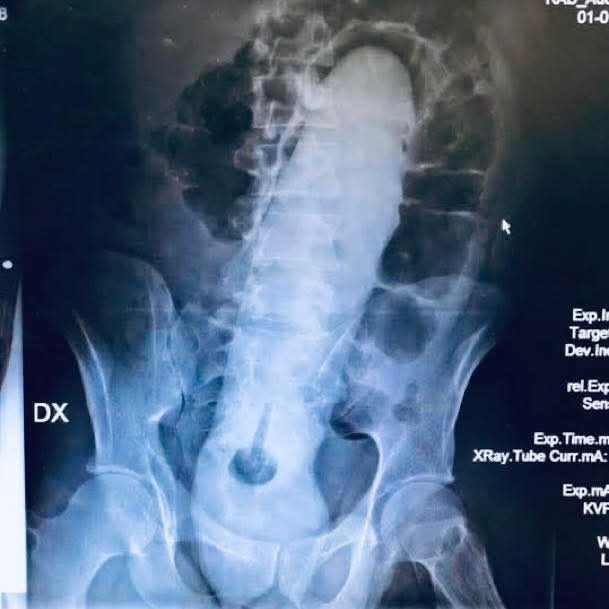

Dazeto Pues a mí la portada me parece bastante chula. Pero me desconcierta que el DIU esté tan a la derecha, desde el total desconocimiento. ¿No debería estar en el centro? ¿Dónde se supone que va el útero?

Teresa Dazeto en el centro pero el cuerpo no es simétrico ni está todo perfectamente alineado. Igual os parece una tontería pero cuando me enteré de que las trompas no están ahí quietas sino que los filamentos se mueven me quedé locatis